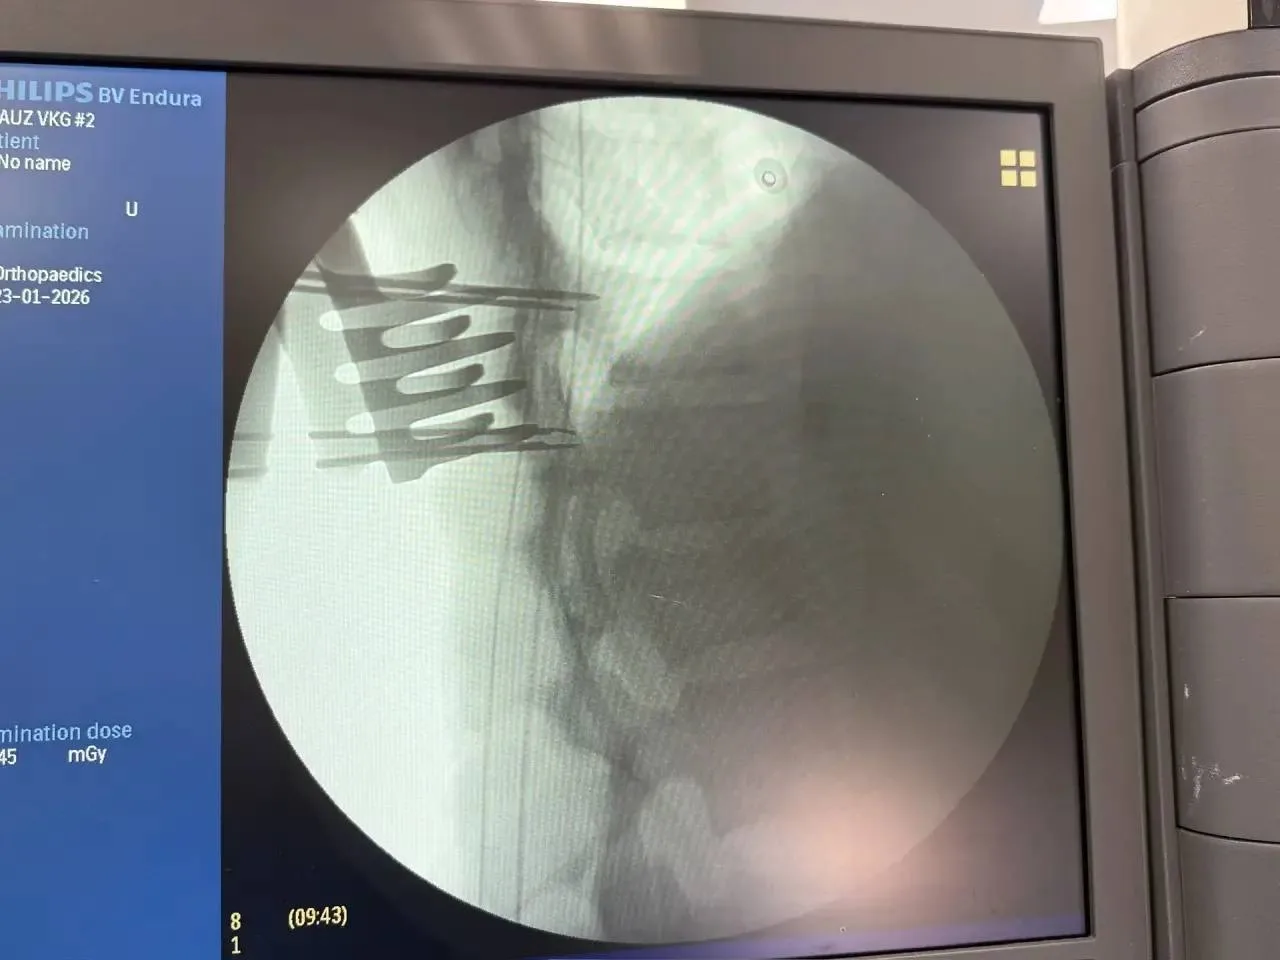

🥼Во Владивостоке нейрохирургии Тысячекоечной больницы вернули способность ходить 18-летней лыжнице с тяжёлой травмой позвоночника

19 января в эту больницу из Арсеньева была доставлена 18-летняя девушка с диагнозом «компрессионный перелом тела позвонка со стенозом позвоночного канала». Травма привела к сдавливанию спинного мозга, что вызвало парез ног и нарушение функций тазовых органов.

Дорога в стационар для этой пациентки выдалась тяжёлой: из-за дорожного инцидента машина скорой помощи резко затормозила, что вызвало у девушки с переломом позвоночника сильнейшую боль.

Нейрохирурги Тысячекоечной провели сложное 4-часовое вмешательство. В ходе операции врачи устранили компрессию нервных структур и стабилизировали позвоночник, установив металлоконструкцию. позволило не только дать спинному мозгу шанс на восстановление, но и полностью исключить риск повторного смещения позвонков.

Уже на вторые сутки после операции врачи начали ставить девушку на ноги, а на четвертые сутки она самостоятельно передвигалась по палате. Сейчас девушка выписана на амбулаторное лечение.